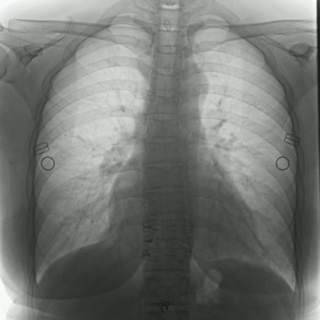

04百微平板,高清成像

普利德多功能動態(tài)DR采用100μm動態(tài)平板探測器,實現(xiàn)5.0lp/mm超高分辨率成像,大幅提升細節(jié)檢測能力;動態(tài)檢查幀率高達30幀/秒,有效避免漏診、誤診;靜態(tài)攝影有效像素高達1800萬,較之于傳統(tǒng)900萬點片像素,圖像細節(jié)更加清晰細膩,有助于醫(yī)生準確判斷病灶的位置、形態(tài)和大小,為急診救治提供可靠依據(jù)。